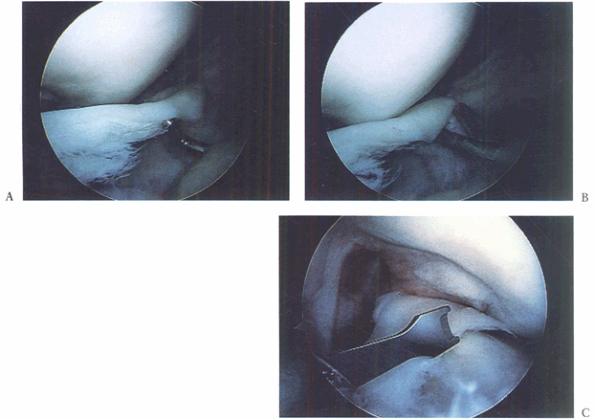

Figure 85.4. A: Displaced bucket-handle tear of the medial meniscus. B: Anterior horn of bucket-handle tear detached. C:

Grasping the resected anterior horn through an inferolateral portal and arthroscopic meniscotome inserted through a transtendon portal to resect the posterior attachment (viewed from inferomedial). (This figure is printed in black and white as Figure 4 of Chapter 85.) |